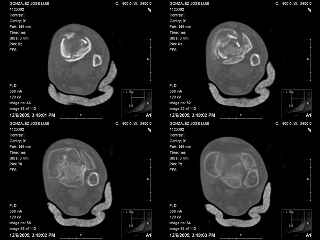

A 56 year old laborer fell off a wall approximately 5 months ago. He sustained an open pilon fracture. He was treated with debridement and external fixation. After he was treated for 4 months, the external fixator was removed.

I have attached his x-rays. I have also attached an WMV movie file of his axial CT (if you are unable to view this, I can post an MPEG file).